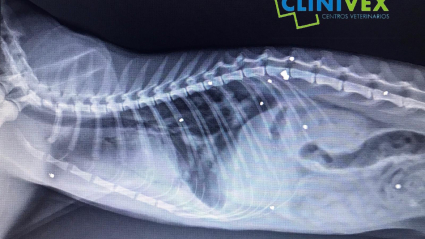

Un gato recibe 10 disparos en una finca de Badajoz